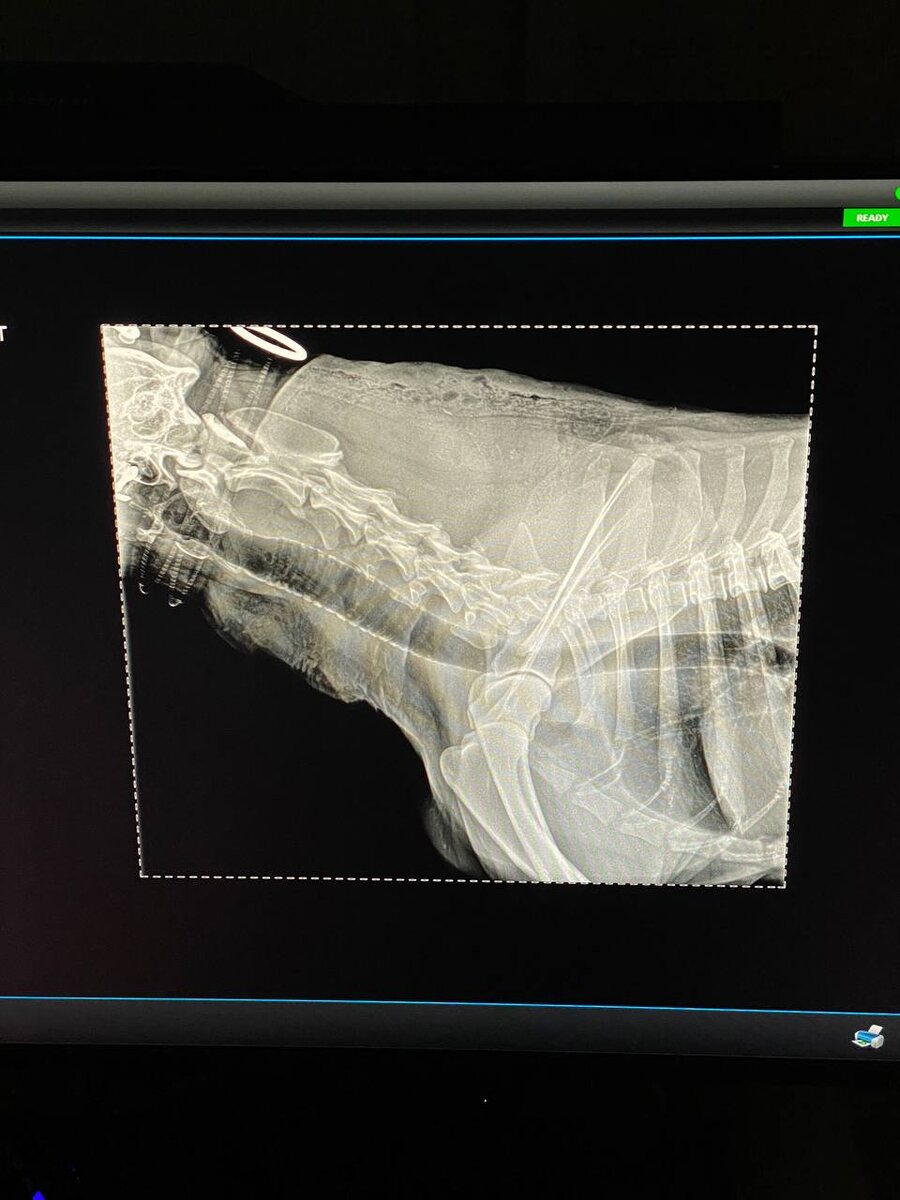

Прокапались на капельнице, поставили дренажи, сделали несколько анализов и уколов, теперь едем к нам